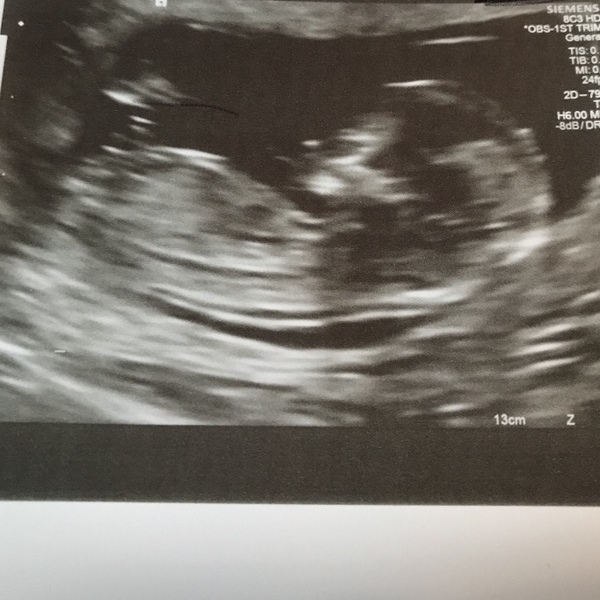

Pictures aren't the best but here they are Grin

August 2018 #3 - booking appointments and 12 week scans!

@YouCantBeSirius wow how exciting :) glad it all went well

Awwww!!! That's made my day looking at your pictures!!! Congrats!!

Beautiful photos @youcantbesirius!

Congratulations on your scan YouCantBeSirius very exciting.

@YouCantBeSirius I’m still on target for 1st August too and had my 12 week scan too! Not the best picture though and sadly we only get one 🙁 good luck to everyone having scans in the coming weeks 😊

Wow! @YouCantBeSirius and @Buk88 these scan photos are making me incredibly excited for my scan on Thursday next week!

So exciting to start seeing the first 12w scans!